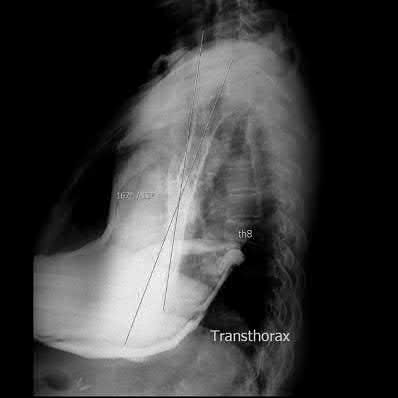

A 35 year-old female presents after prolonged extrication from a motor vehicle collision complaining of severe pelvic pain. Physical examination reveals diminished perianal sensation. She is otherwise neurologically intact. Figures A through D are radiographs and representative CT cuts of her injury. Which of the following nerve roots has likely been injured by the acute trauma?

The clinical scenario is consistent with a high-energy sacral fracture. The radiographs in figures A and B demonstrate a sacral fracture with posterior displacement of the right hemipelvis seen on the inlet view. Figures C and D are axial and sagittal CT images which show a displaced fracture of the right

hemisacrum along with a transvere fracture component through the S3 body . Diminished perianal sensation is concerning for an S2 nerve root injury.

Mehta et al reviewed the current management of sacral fractures. They note that the S1 and S2 nerve roots are more likely to be injured with sacral fractures as they occupy 1/3 to 1/4 of the neural foramina, as opposed to S3 and S4, which only occupy 1/6 of the neural foramina.

Robles reviewed the current literature to ascertain principles of evaluation and treatment for transverse sacral fractures. The author notes that injury to nerve roots S2 to S5 is manifested by impairment of urinary and anal continence and sexual function.

The first illustration demonstrates the sacral nerve root dermatomal distribution. The second shows a pelvic cadaver dissection demonstrating the sacral nerve roots as they exit the foramina.